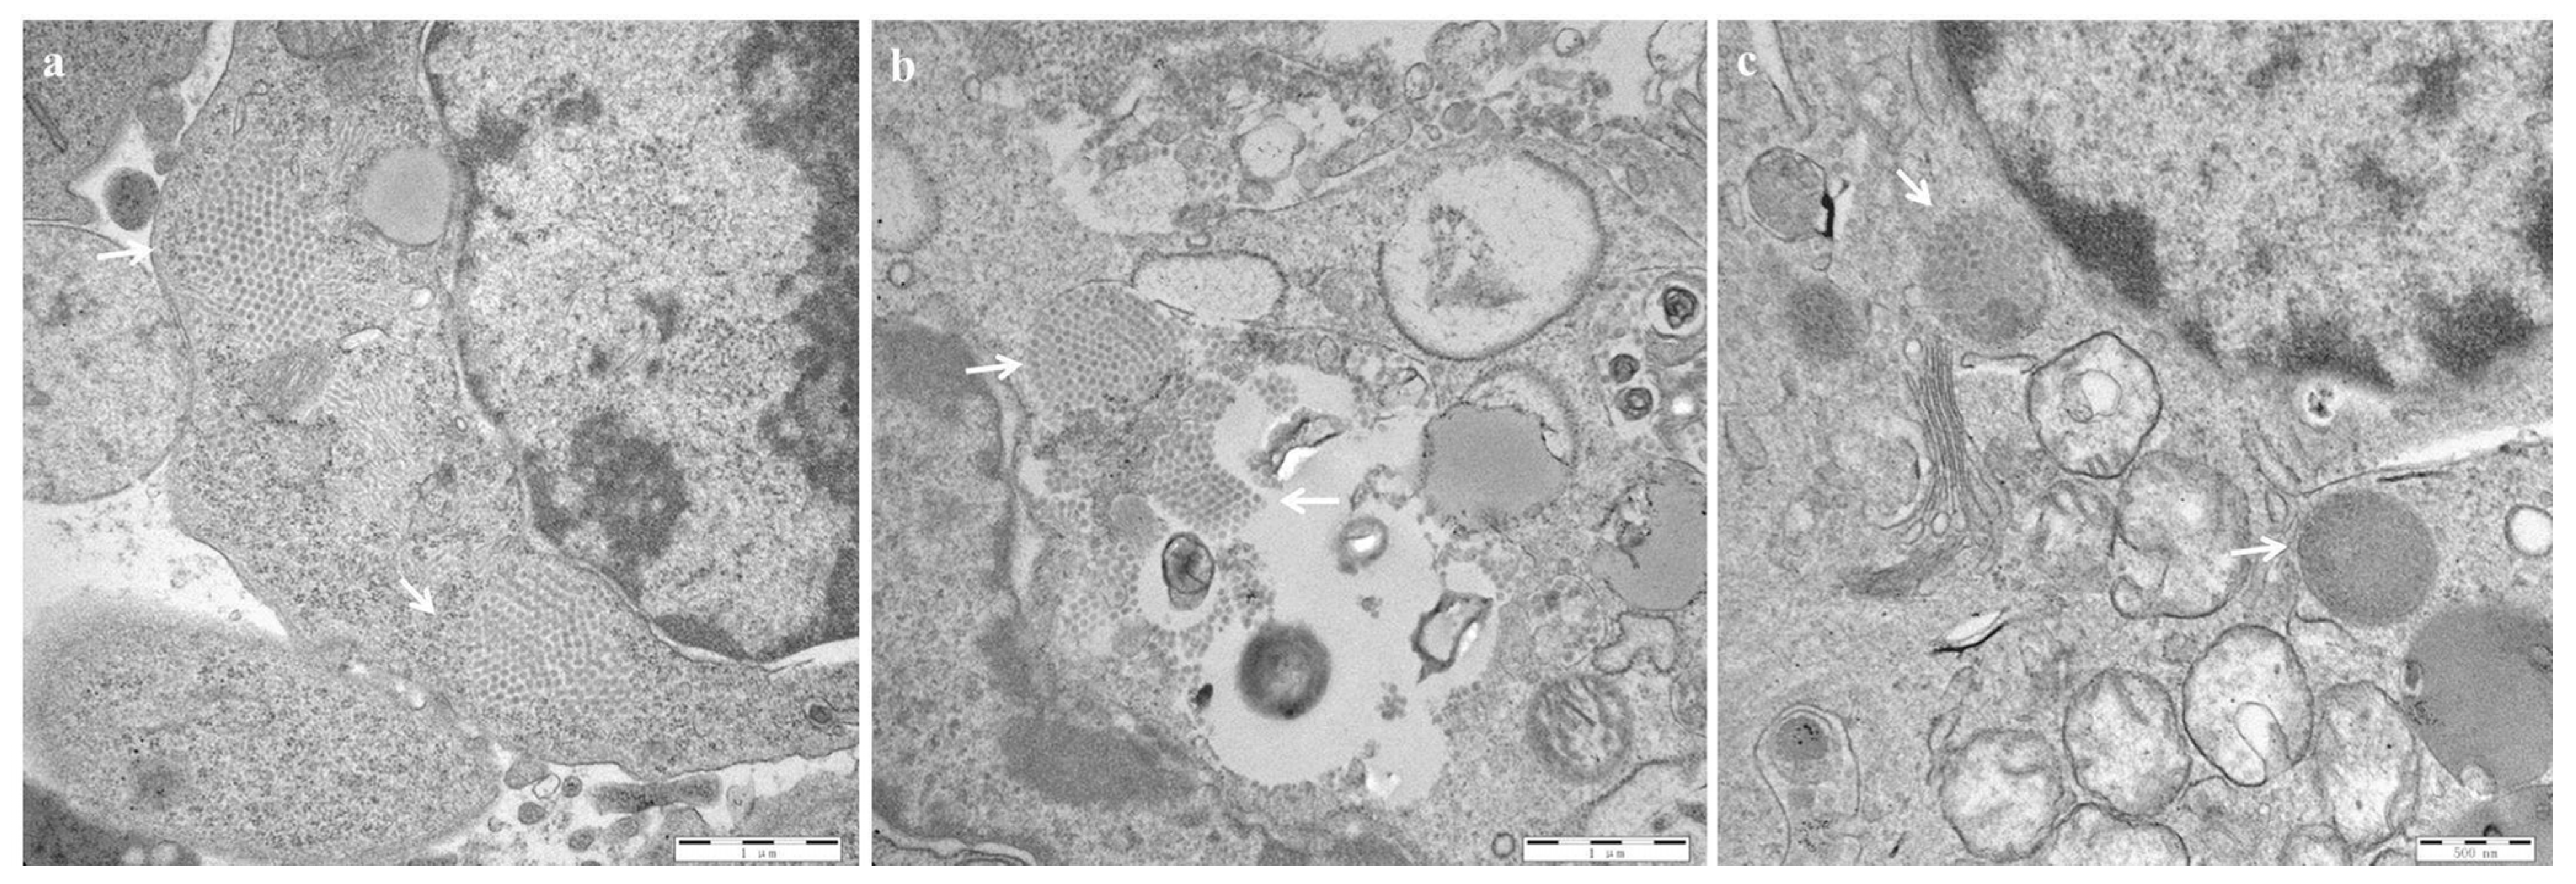

EM observations showed that virus particles arranged in a lattice pattern with a diameter of approximately 60 nm could be seen in the cytoplasm of the bursal tissues of both the HLJ0504 (Figure 6a) and SHG19 groups (Figure 6b) at 60 h p.i. For the Gt group, virus particles were not observed at 60 h, 72 h, and 5 d p.i.; relatively few IBDV were observed only at 14 d p.i. (Figure 6c).

Figure 6.

Electron microscopic observation of the infectious bursal disease virus (IBDV) in the bursa. (a) HLJ0504 group. (b) SHG19 group. (c) Gt group. The IBDV particles arranged in a lattice pattern were marked by a white arrow.

The results of this study showed significant differences in clinical signs and tissue damage caused by IBDV strains with different virulence in infected chickens. The vvIBDV strain (HLJ0504) had the highest pathogenicity, the highest replication efficiency, the ability to cause significant damage to the bursa and other organ tissues, and high fatality. The virus was distributed in almost all organs, with the highest titers in the bursa, followed by the caecal tonsil, spleen, and thymus. High viral titers were also detected in the blood, with the 60 h p.i. to 4 d p.i. period being a period of severe viremia. EM observation showed that a large number of IBDV virion scattered in a lattice pattern were found in the infected bursa. Furthermore, analysis of the cloacal swabs revealed that the HLJ0504 group had significant virus excretion. The apparent signs, the reflection of in vivo lesions and viral proliferation, included the onset of depression in infected chickens from 48 h p.i., the peak period of death at 3–5 d p.i., and the final mortality of 80%. The cause of bursal atrophy is essentially the atrophy of the lymphoid follicles and the breakdown and necrosis of B lymphocytes. The vvIBDV has been shown to induce changes in cytokine levels within the bursa, promoting inflammation and disturbance of the tissue microenvironment, which is a strategy to reduce the activity of B lymphocytes that the virus uses to escape or suppress the immune responses of the host [25,26,27].

The attenuated strain (Gt) was non-pathogenic, with slow replication and low titer. No significant clinical, autopsy, or pathological signs or lesions were observed in chickens inoculated with Gt, which was significantly different from vvIBDV and nVarIBDV. After Gt infection, low levels of viral replication were detectable only in the bursa, and only a small amount of clustered lattice-like IBDV particles were observed in the bursa at 14 d p.i, and there were no significant virus excretions from the infected chickens. The difference in the in vivo replication efficiency of the virus is an important influencer of the difference in the pathogenicity of different strains [28,29]. Furthermore, virus strains with different virulence could trigger different levels of immune response. The rate and titer of antibody production have been shown to be related to the degree of in vivo virus replication [30].